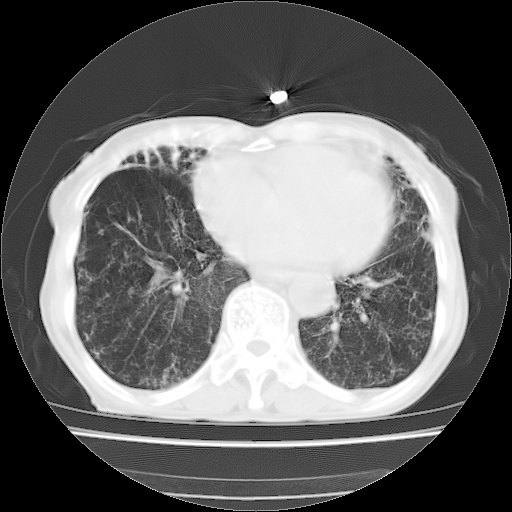

病人发热、气促就诊。原二周前已行ct扫描,当时诊断为双肺下叶、右肺中叶支气管扩张并感染,双肺上叶片状渗出性病变。今天复查胸部ct,双肺下叶支气管扩张并感染病灶较前明显吸收,但双肺上叶渗出性病变较范围较前明显增大。

现传今天ct图像给大家讨论。

双肺多发大片状、斑片状高密度渗出影,部分实变,考虑病毒性肺炎。